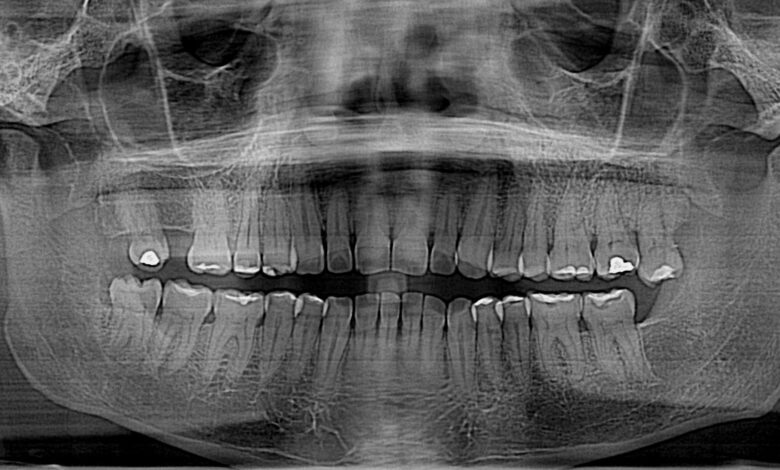

Los dientes son como piezas de un rompecabezas que deben encajar de cierta forma entre sí, como si formasen una cremallera.

Grosso modo, no debe haber piezas dentales apiñadas o excesivamente separadas, y los dientes superiores deben superponerse ligeramente por delante de los inferiores, mientras que los laterales estar en estrecho contacto. Esto garantiza una masticación efectiva y eficiente.

En caso contrario, cuando los dientes y la mandíbula no encajan correctamente al morder —en lo que se conoce como desalineación dental o maloclusión— las consecuencias no son solo estéticas como la mayoría de las personas cree. Desafortunadamente, muchos no ven la necesidad de corregir esta situación o acuden tarde, sin saber que sus efectos pueden extenderse.